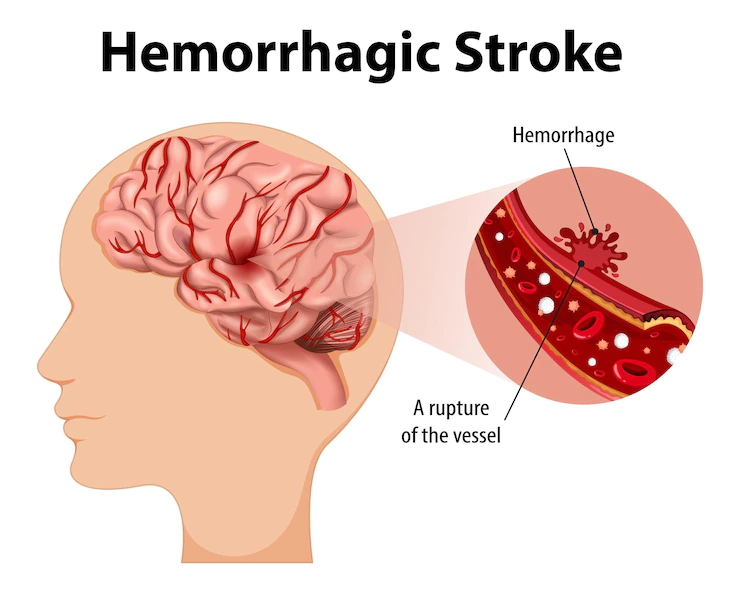

A brain hemorrhage is a type of stroke & caused by an artery in the brain bursting and causing localized bleeding in the surrounding tissues.

A brain hemorrhage, also known as a cerebral hemorrhage or intracranial hemorrhage, occurs when there is bleeding in the brain. This can happen due to various reasons, such as a ruptured blood vessel or trauma. The bleeding can compress surrounding brain tissue and lead to serious complications.